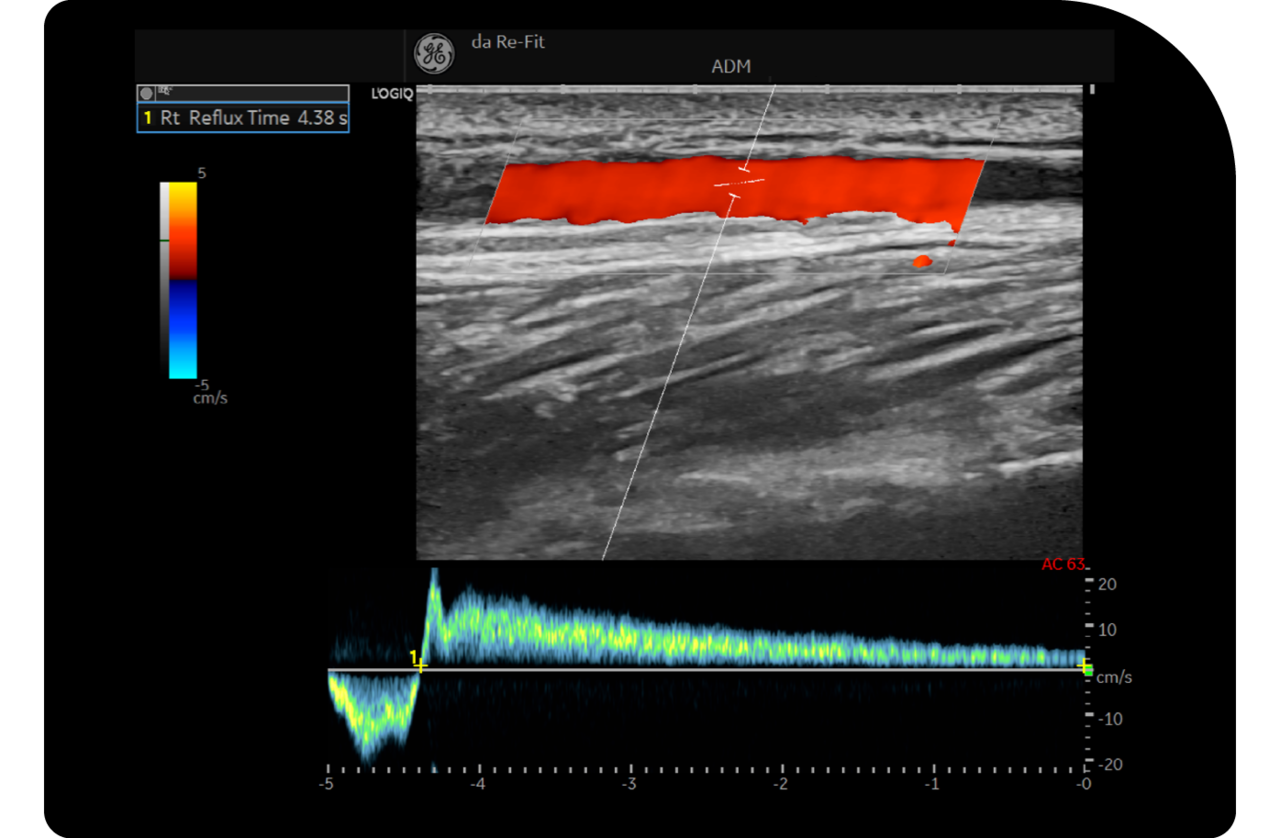

도플러 초음파 정밀 검사

초음파 정밀 검사를 통해 다리의 상태를 실시간으로 확인하여

혈관의 확장 정도, 혈액의 역류 상태 등을 정확하게 진단합니다.

검사 결과를 바탕으로 하지정맥류의 심각도를 판단하고

이를 통해 최적의 수술 또는 치료 방법을 결정합니다.